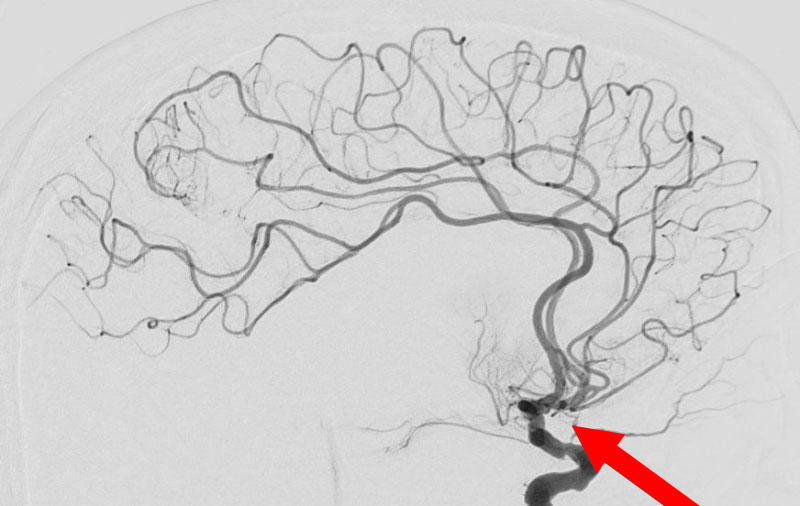

No.1596 手術後